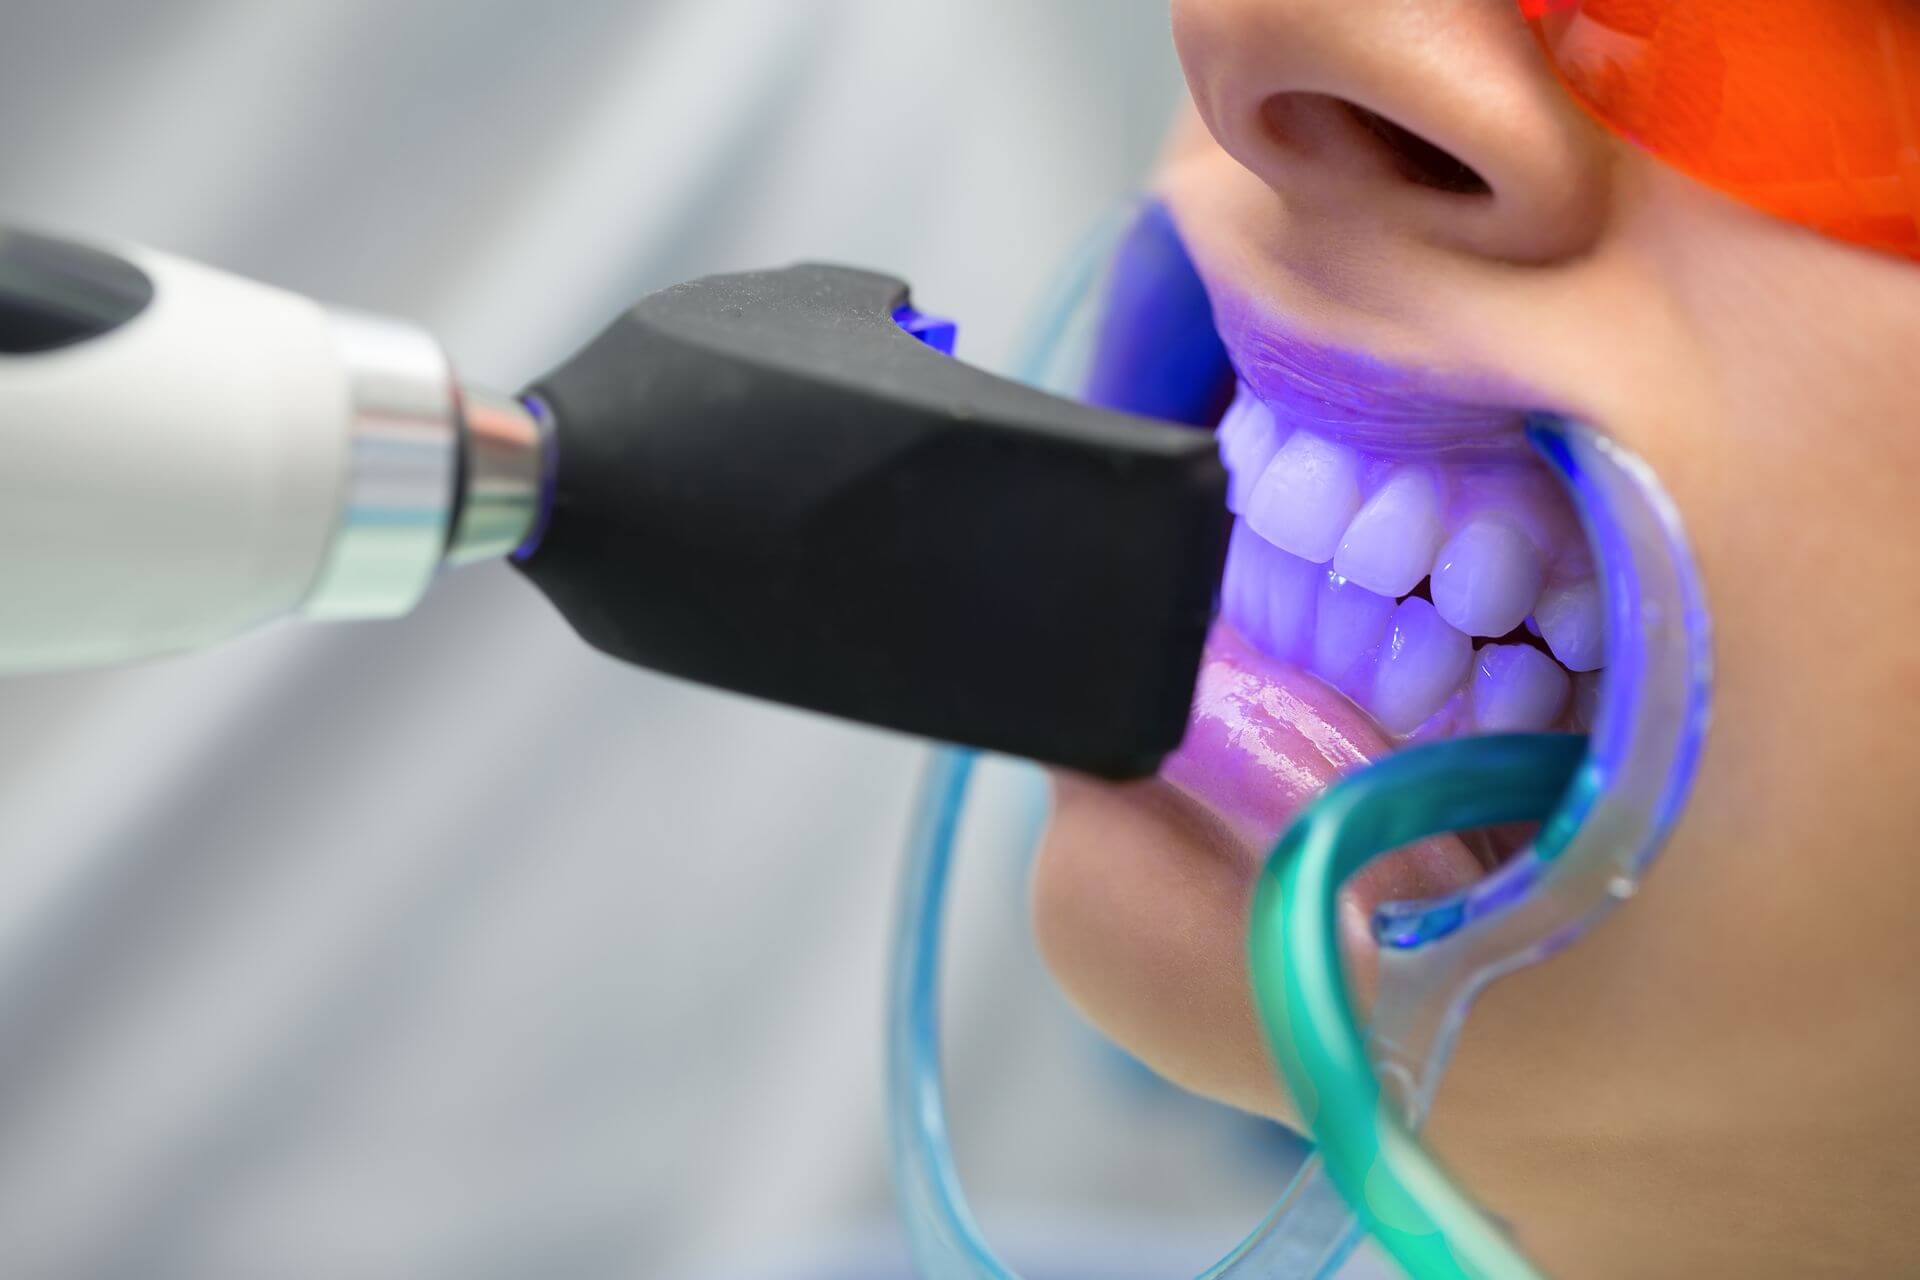

Quando si parla di igiene orale quotidiana, la maggior parte delle persone pensa subito allo spazzolino e al dentifricio. In realtà, per mantenere davvero sani denti e gengive, esiste un alleato fondamentale che spesso viene sottovalutato: il filo interdentale. Perché lo spazzolino da solo non basta Lo spazzolino è essenziale per rimuovere la placca batterica dalle…